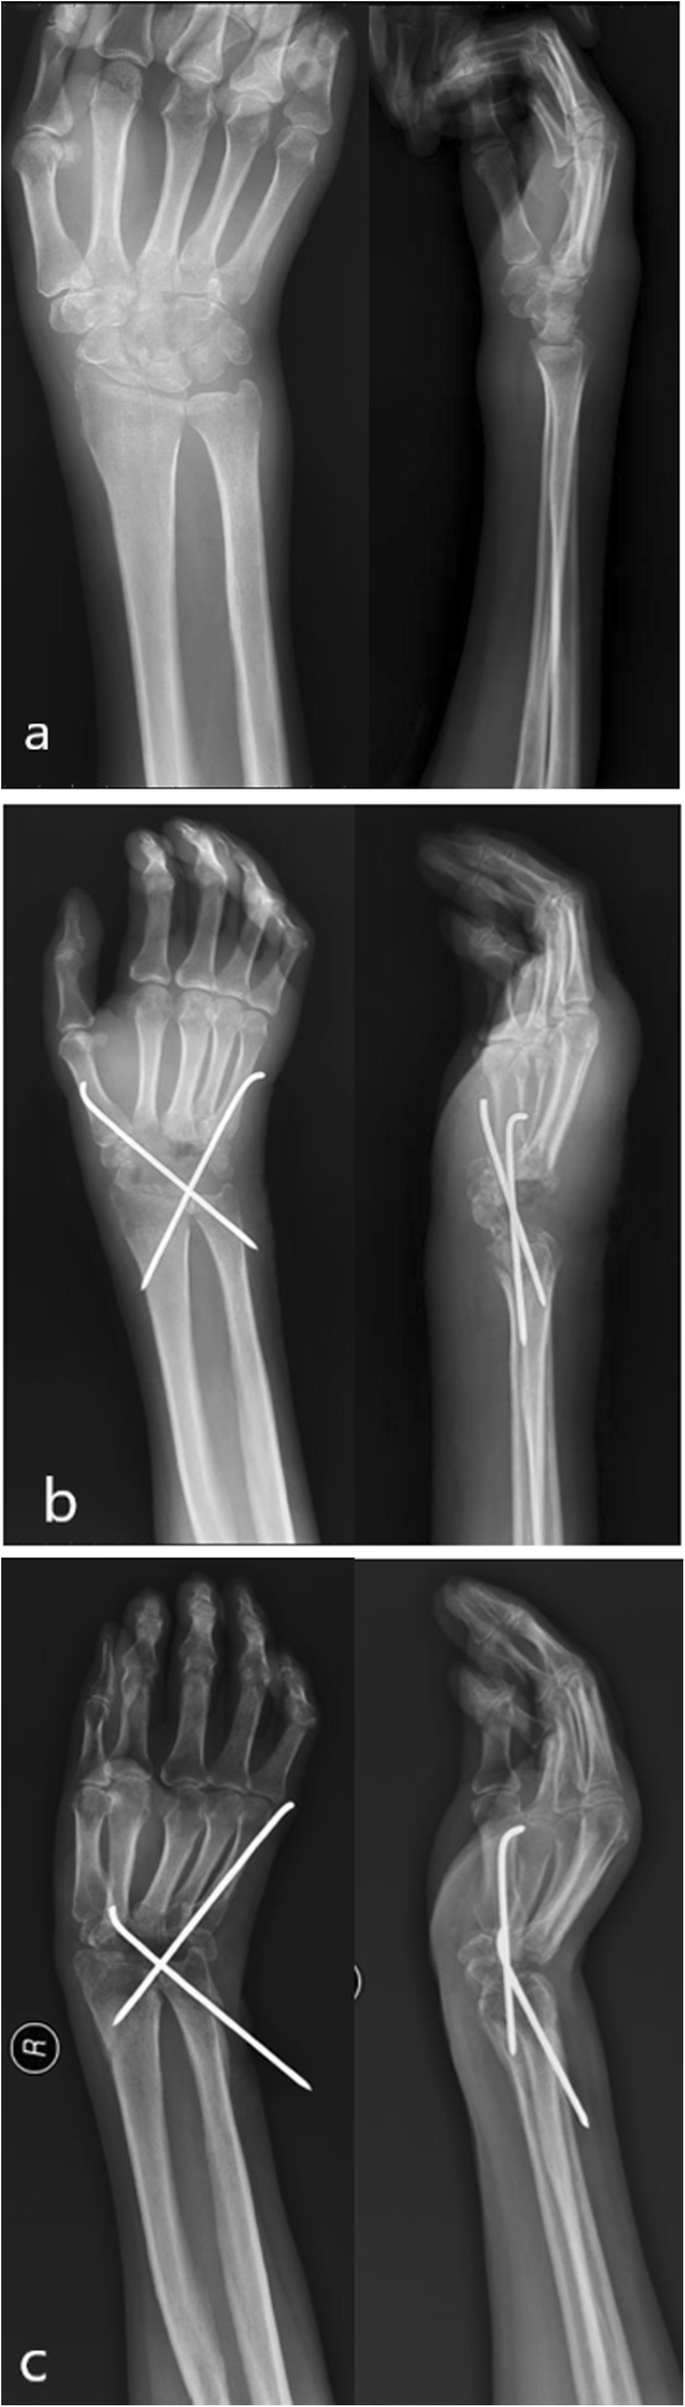

Early use of anti-tuberculosis drugs is key to successful treatment [18]. In our study, five patients received antecedent surgical clearance of the focus of the wrist. However, they were not given anti-tuberculous postoperatively, a factor that likely contributed to the recurrence of wrist tuberculosis. Surgical debridement without prescription of chemotherapeutic agents may lead to the recurrence of wrist tuberculosis [26]. During operation, it is advisable not to excessively pursue a small incision. Instead, it is essential to fully expose the focus, protecting the blood vessels and nerves of the wrist, and thoroughly remove the focus tissue, especially the caseous substance and rice bodies, including the necrotic carpal bone, tendon, tendon sheath, and the surrounding soft tissue, and to fully scrape the focus tissue with a curette until the normal bone surface and tissue ooze blood. In case of a severely erosion of the carpal bones, the wrist function of cannot be restored after removing the necrotic bone, joint fusion can be performed. Arthrodesis can be performed with steel plates or Kirschner wires. The steel plate should be used for internal fixation if there are more necrotic carpal bones and if the wrist joint is unstable after more carpal bones are removed. Compared to the Kirschner wire, the steel plate fixation is more reliable; however, the cost is higher. If there is a small amount of wrist bone removal and if the Kirschner wire can be fixed firmly, the patient and their guardian should be consulted. A Kirschner wire fixation may fix the wrist in a deformed position. Among the three cases of wrist fusion, 2 were fixed with a steel plate and the fixation position of wrist joint was good. One case was fixed with a Kirschner wire and resulted in a slightly deformed wrist joint (Fig. 3).

a Conventional radiography anterior posterior and lateral view pre-operation; b X-ray scan 1 month post-operation, the position of the Kirschner wire is not shifted; c X-ray scan 8 months post-operation, the position of the Kirschner wire is significantly displaced and the wrist is fused in a position towards the ulnar deviation region